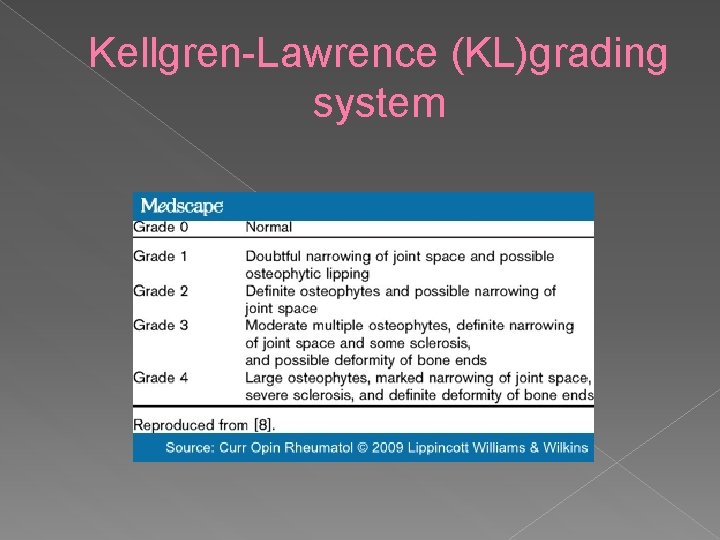

Kellgren-Lawrence (KL)grading system